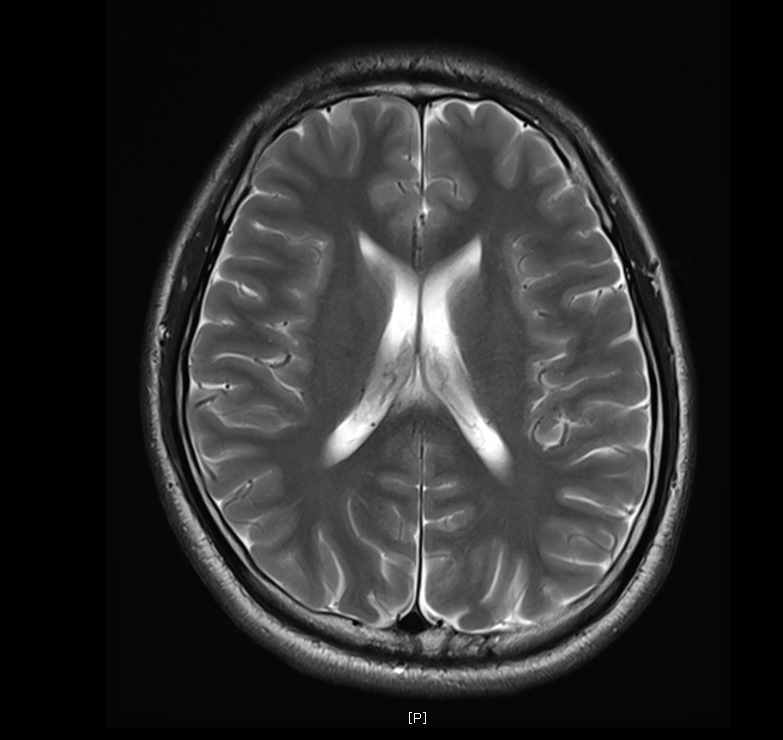

지난 금요일에 MRI를 촬영했는데요

혈관같기도 하고 하얀색 붕붕 뜨는 게 있어보이는데 (혈관같음)

한번 봐주실수 있나요? 그리고 전체적으로 괜찮은지도 봐주시면 감사하겠습니다.

특별하게 눈에 띄는 병변은 있어보이지 않습니다

말씀하신 것은 혈관의 가능성이 높겠습니다